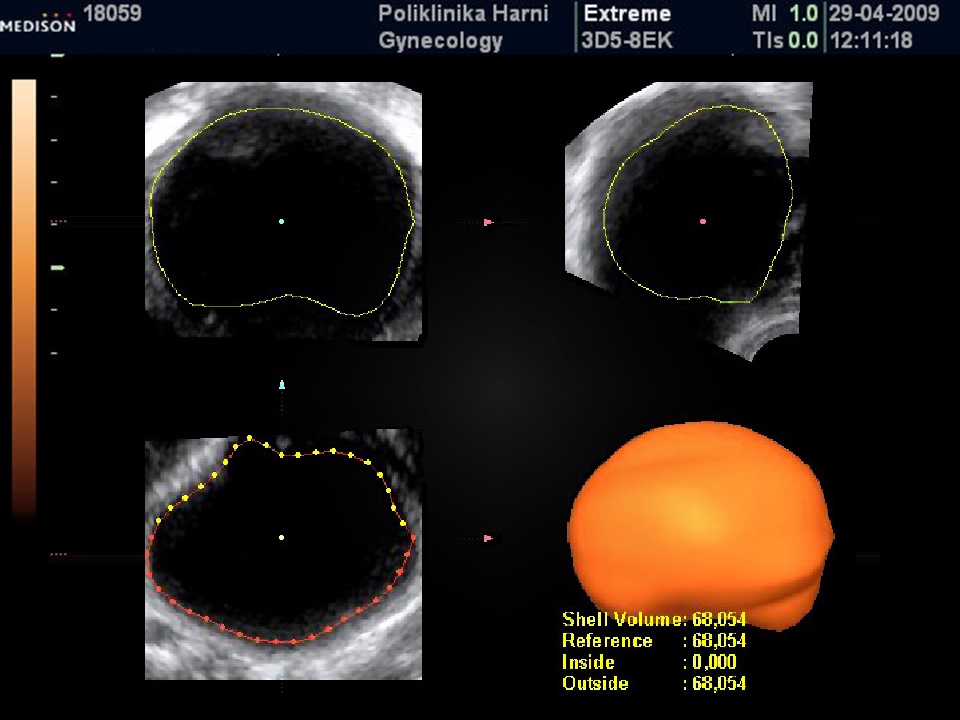

Mjerenje tumorskih tvorbi

Uvijek se mjere 3 ortogonalna dijametra. Mjeri se u projekciji u kojoj procijenimo da je struktura najveća. Prvo se mjeri longitudinalna duljina i anteroposteriorni dijametar, zatim se struktura okrene za 90 stupnjeva i mjeri zadnji dijametar.

Kako se mjeri papilarna projekcija?

Mjeri se najveća papilarna projekcija u tri ortogonalna dijametra. Kada se mjeri visina ne smije se u mjeru uključiti stijenka ciste ili septuma.